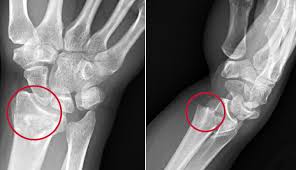

Colles’